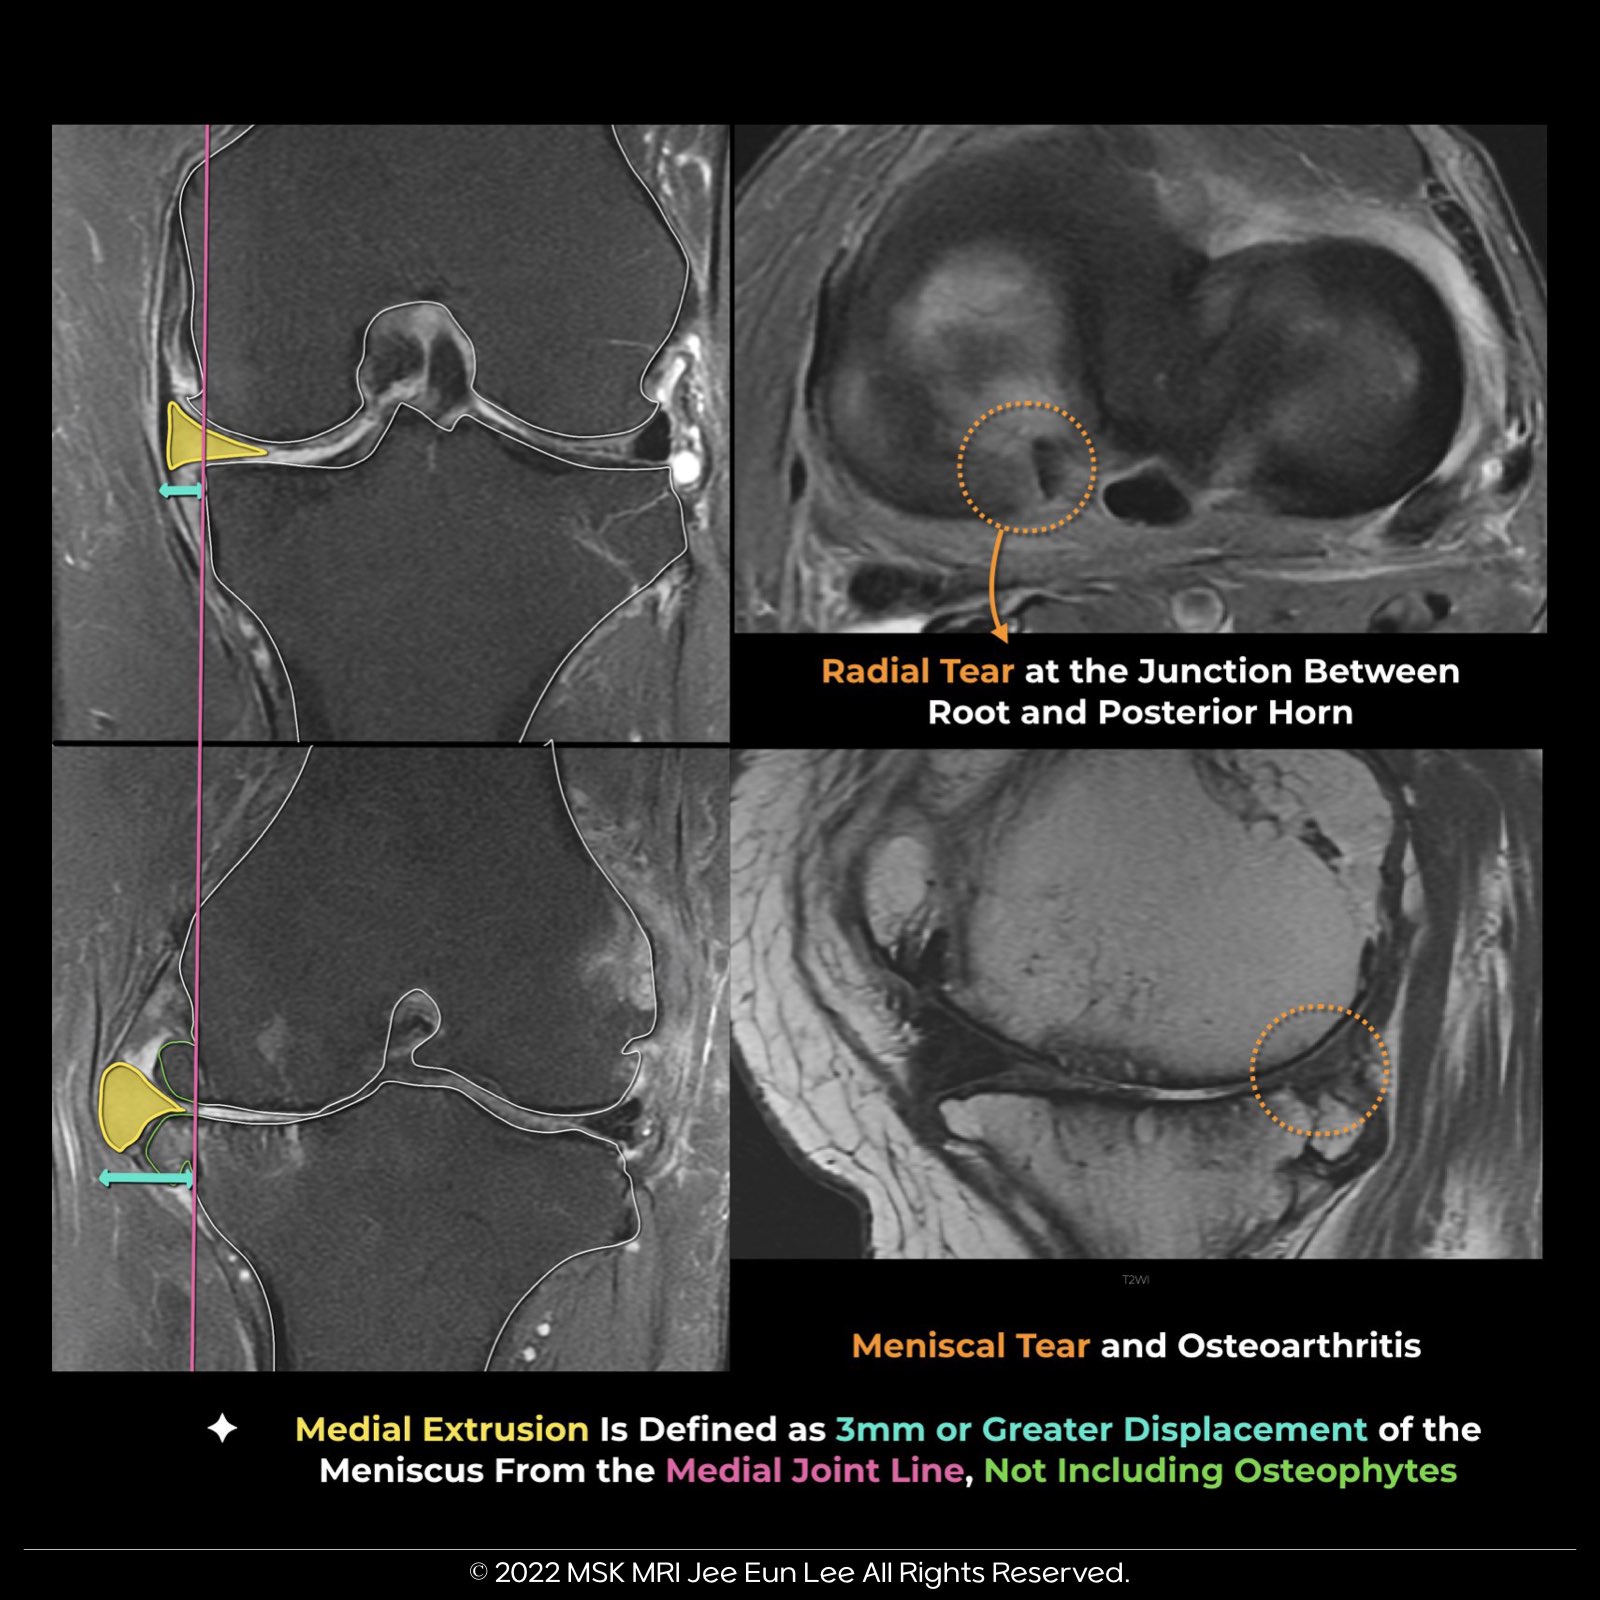

- Meniscal extrusion occurs when the meniscus extends 3 mm or more beyond the tibial plateau edge.

- Substantial medial meniscus extrusion (> 3 mm) indicates severe meniscal issues like degeneration, extensive tears, and root involvement.

- Extrusion is commonly associated with posterior root tears but can also be caused by large radial tears, osteoarthritis, and knee malalignment.